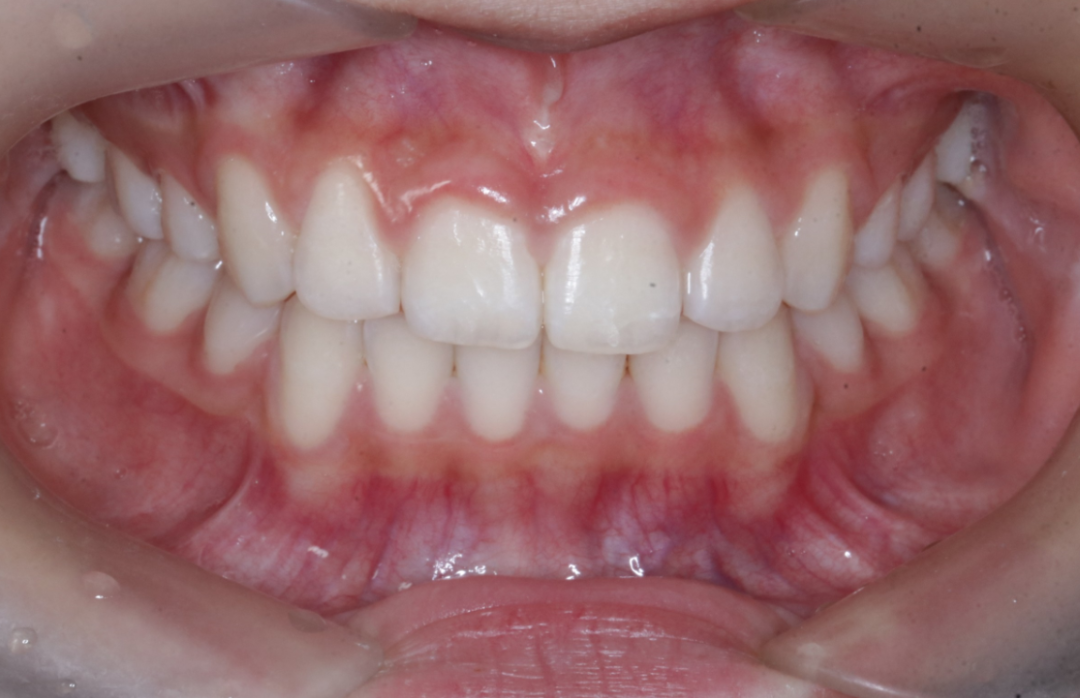

治疗前                        治疗后

儿童错合畸形早期矫治是阻断影响儿童颌骨、牙齿正常发育的因素,促进颌面部正常发育,降低II期矫正的难度,减少II期矫正的时间,甚至不需要II期矫正。让孩子早期获得自信,绽放灿烂笑容。

术前→术后